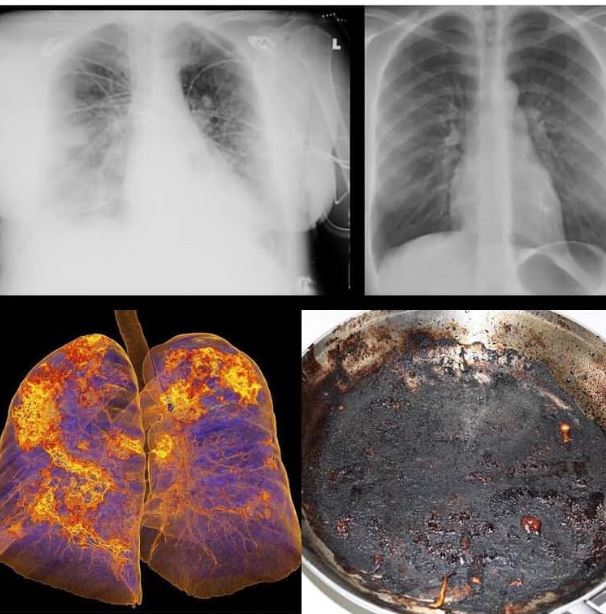

Хэт хүнд туссан хүмүүсийн уушгийг эдгэснийх нь дараа рентгенээр харахад түлэгдээд, дагтаршсан хайруулын тавагтай төстэй байсан хэмээв

Хэт хүнд туссан хүмүүсийн уушгийг хараар хэлэхэд түлэгдээд,дагтаршсан хайруулын тавагтай л адил болох боломжтой гэж зүйрлэсэн байна шүү.

Хөнгөн туссан хүмүүс ч уушиг нь заавал нэг сэвтэй болж үлдэж байна гэсэн.

Монгол-Япон эмнэлэг өвчтөнүүдийнхээ уушгийг эдгэснийх нь дараа рентгенээр харсан байна.

Ингэж бодохоор сэтгэл санаа навс унах юмдаа. Бас дээрээс нь амьдрах хугацаа 8 жилээр дор хаяж багасдаг хэмээн ярьсныг хав дарсан байх юм.